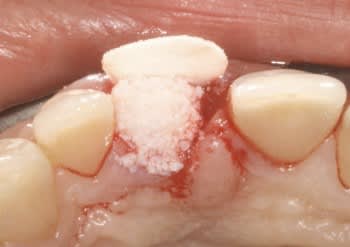

Ci joint cas avec membrane résorbable laissée exposée volontairement ( technique Bio coll proposée par Anthony G. Scar dans les années 2000 remis au gout du jour par tarnow en 2006 ).

Celà ne marche pas avec toutes les membranes...

fig 4 pose membrane résorbable + os xénogène

fig 5 membrane suturée

fig 6 réouverture J0 + 6mois